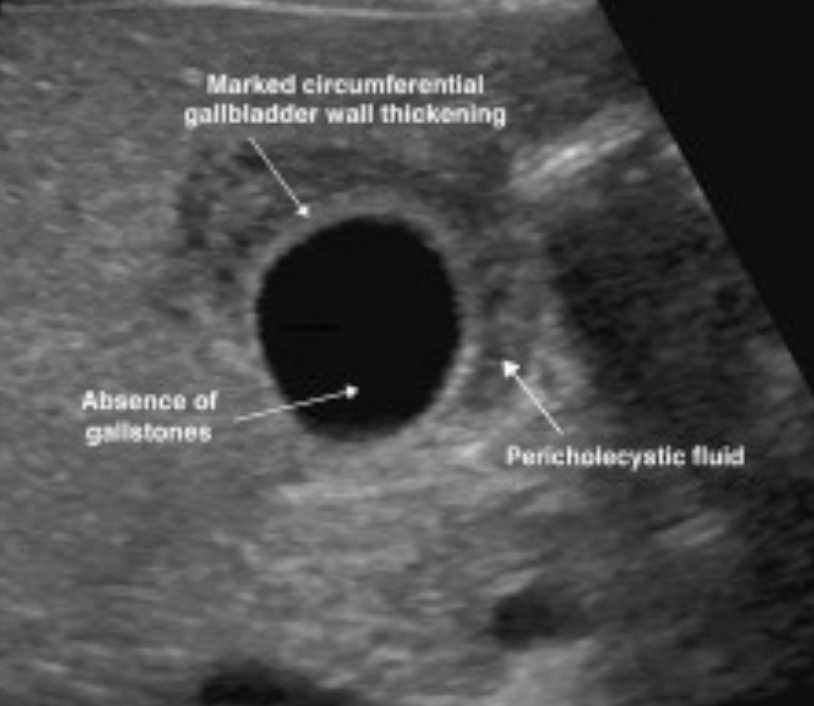

What is often the first line imaging method to identify a patient with acute cholecystitis?

1 - ultrasound

2 - CT scan

3 - MRI

4 - chest X-ray

A

• can identify gallstones, thickened gall bladder wall, distended gall bladder, pericholcystic fluid (fluid surrounding gall bladder) and sonographic Murphys sign